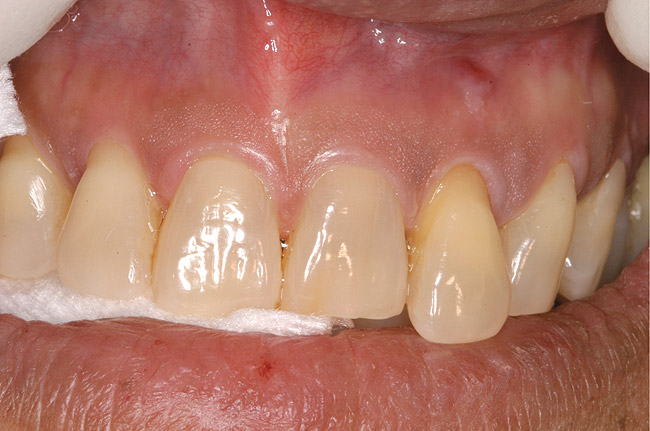

Figure 1  Tooth No. 5 showing advanced periodontal bone loss and a widened periodontal ligament space.

Figure 1

Figure 5  Recurrent decay of teeth Nos. 11 and 12. Note the proximity of the decay on both teeth to the osseous crest.

Figure 5